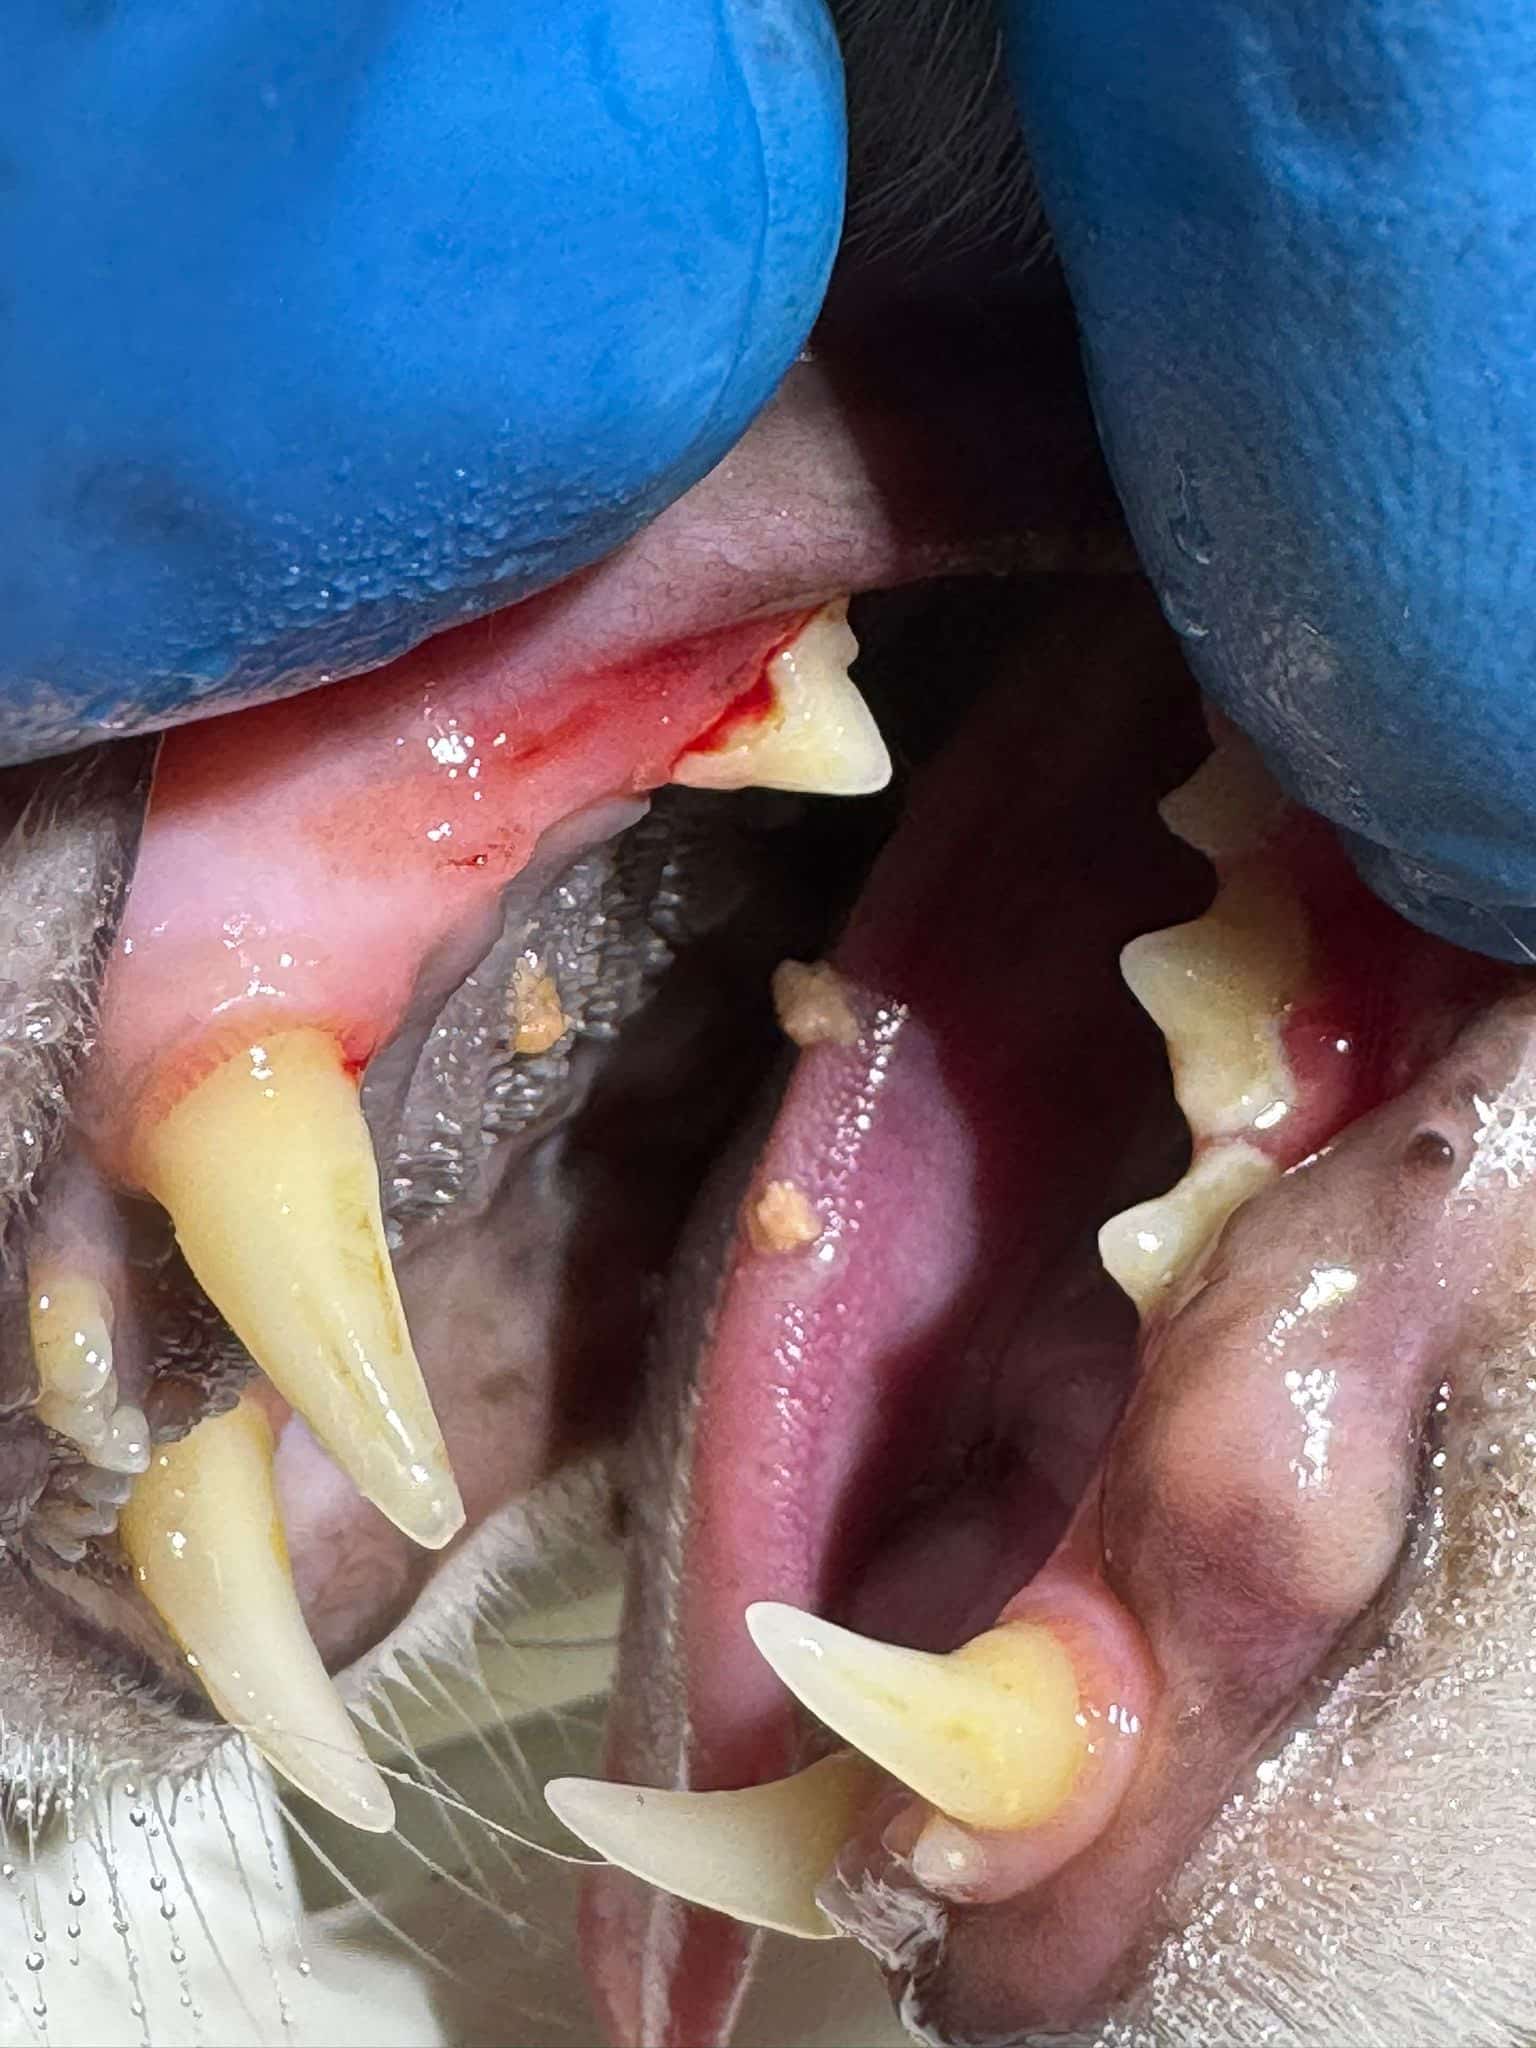

Beispielbilder vorher - nachher

Vorher

Nachher

Beispielfotos unserer Patienten

Das sollten Sie behandeln lassen!

Wir entfernen den Zahnstein vollständig und professionell